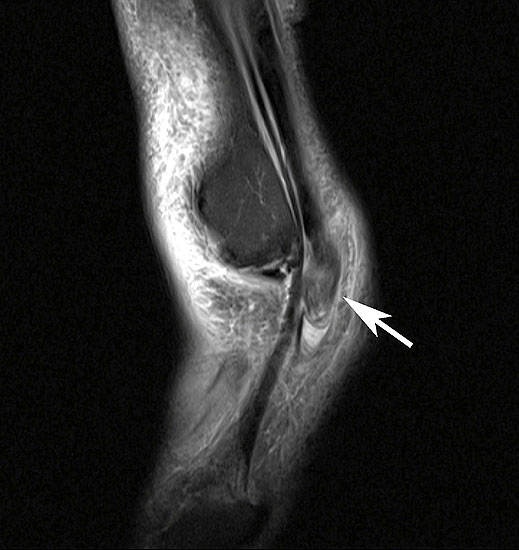

MRT

Unterbrechung des Retinakulums als indirektes Zeichen einer traumatischen Peronealsehnenluxation im MRT.

Neben der klinischen Untersuchung besitzt in der Diagnostik von Sehnenpathologie das MRT mit Kontrastmittel einen hohen Stellenwert 8910. Kontrastmittelaufnahme in die Sehne ist immer als Hinweis auf einen Riss zu werten. Weiterhin ist Flüssigkeit im Sehnengleitlager oder die Aufnahme von Kontrastmittel in das Sehnengleitgewebe ein indirektes Zeichen einer Sehnenpathologie.

Springt die Sehne spontan in ihr Gleitlager zurück, ist das MRT ohne Kontrastmittel häufig unauffällig, mit Kontrastmittel ist regelhaft eine Signalveränderung des Retinakulums erkennbar. Kommt es nach einem Trauma spontan zu einer Reposition der Peronealsehnen, so kann eine konservative Behandlung mit sechswöchiger Ruhigstellung des Sprunggelenks im Unterschenkelgips versucht werden. In etwa 50% der Fälle kann so eine narbige Heilung des Retinakulums erreicht werden 25, in den restlichen Fällen bleibt eine Instabilität bestehen. Kommt es zu keiner spontanen Reposition der Sehnen, besteht primär die Indikation zur operativen Rekonstruktion. Eine chronische Instabilität ist durch konservative Maßnahmen nicht zu beeinflussen. Die Indikation zur operativen Stabilisierung ergibt sich aus dem Leidensdruck.